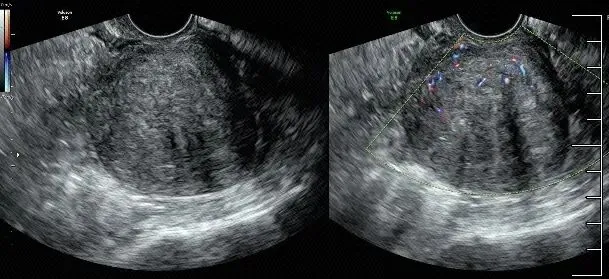

局灶性子宫腺肌病,边界不清,未见明显包膜,内部血供增多。

子宫增大,子宫后壁比前壁肌层厚,后壁肌层呈栅栏样改变(箭头示)